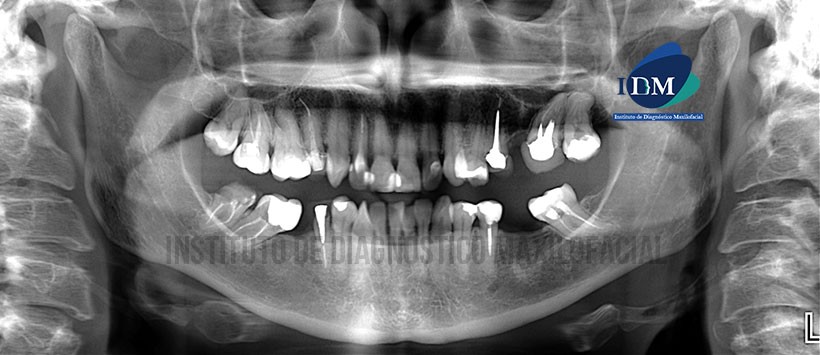

Paciente de sexo femenino de 50 años de edad acude al Instituto de Diagnóstico Maxilofacial para evaluación imagenológica de la pieza 12.

A la evaluación de la radiografía panorámica, se evidencia la presencia de múltiples piezas con material de obturación de conductos, espigo, coronas protésicas, así como múltiples piezas ausentes (Figura 1). Posteriormente se obtuvo una radiografía periapical de la zona a evaluar, donde visualizo que la pieza 12 presenta material de restauración en zonas proximales, aparente espigo de material radiopaco y material de obturación de conducto. Cabe resaltar la ausencia de lamina dura en mesial de la en mención, así como una aparente disminución de la densidad ósea de ese mismo lado. (Figura 2)